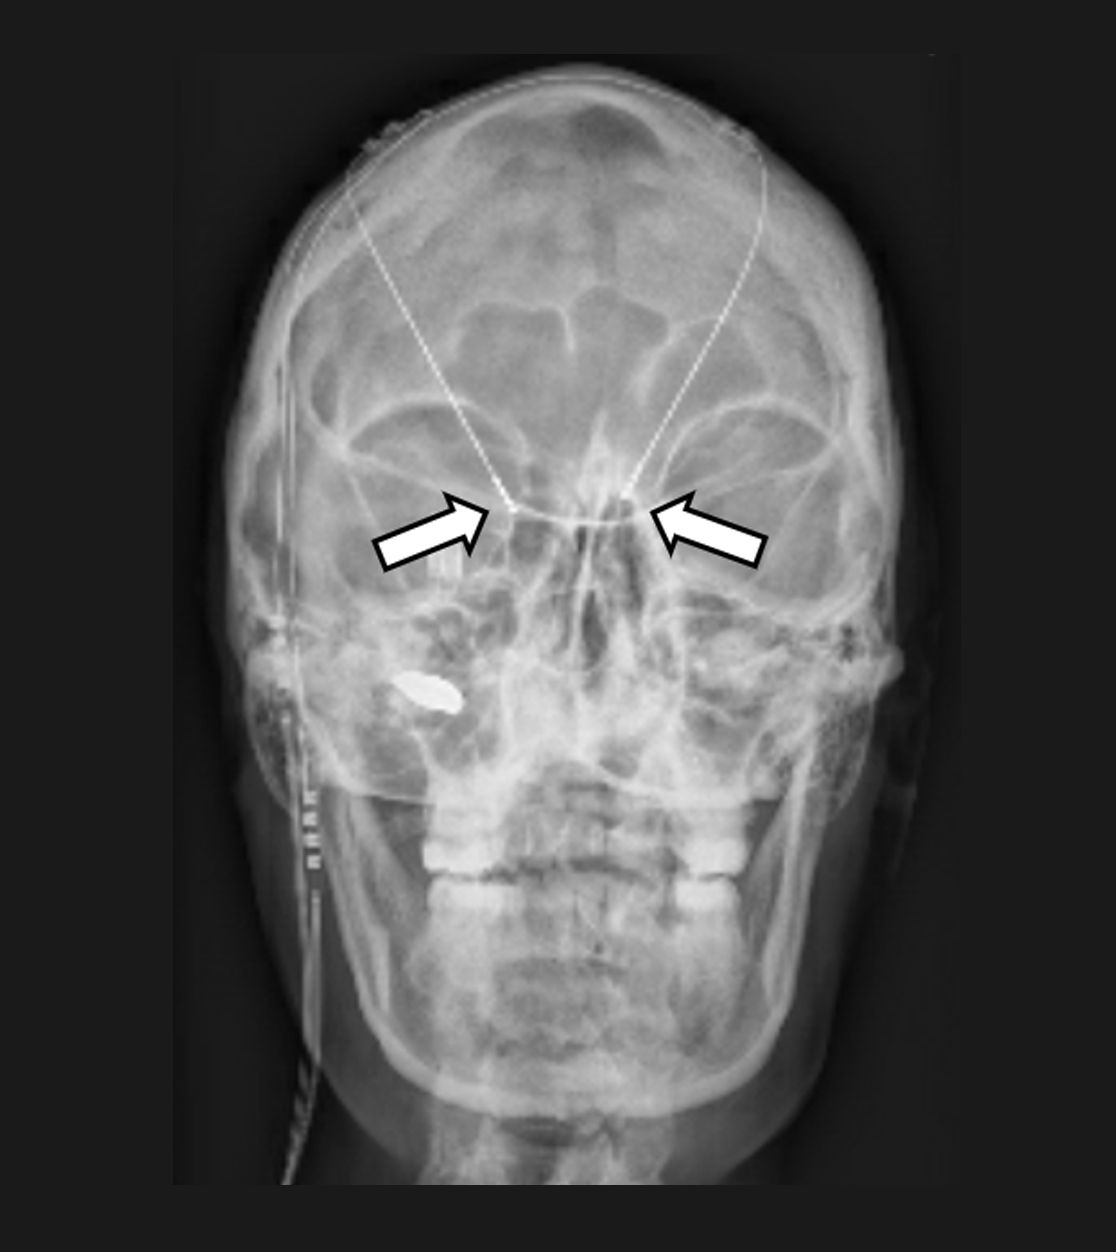

Die Tiefe Hirnstimulation, welche meist für Patienten mit Bewegungsstörungen wie Parkinson oder einer Dystonie eingesetzt wird, kann auch bei Patienten mit chronischen Gesichtsschmerzen oder einem sog. zentralen Schmerz zur Anwendung kommen. Es werden Elektroden gezielt mittels sog. stereotaktischer und robotischer Verfahren in kleine Kerngebiete des Gehirns implantiert und – wie bei anderen neuromodulativen Verfahren – an einen Impulsgeber (vergleichbar mit einem Herzschrittmacher) angeschlossen. Durch die Abgabe angepasster elektrischer Impulse sollen dann die Schmerzen gelindert und somit die Lebensqualität der Patienten verbessert werden. Wie bei der Motorcortexstimulation muss die Möglichkeit einer Tiefenhirnstimulation zur Schmerztherapie stets individuell evaluiert werden.

In das Gehirn implantierte Elektroden zur Tiefen Hirnstimulation (Pfeile)

Impulsgeber im Bereich des Brustkorbs